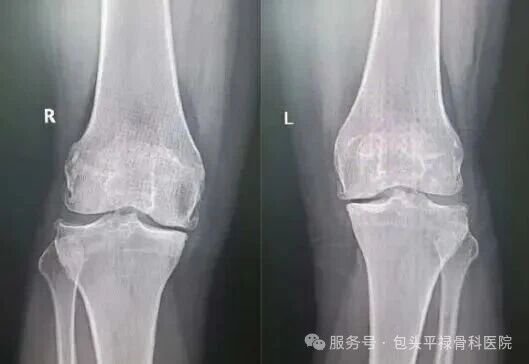

通过X光片看到,磨损确实局限在一个间室内